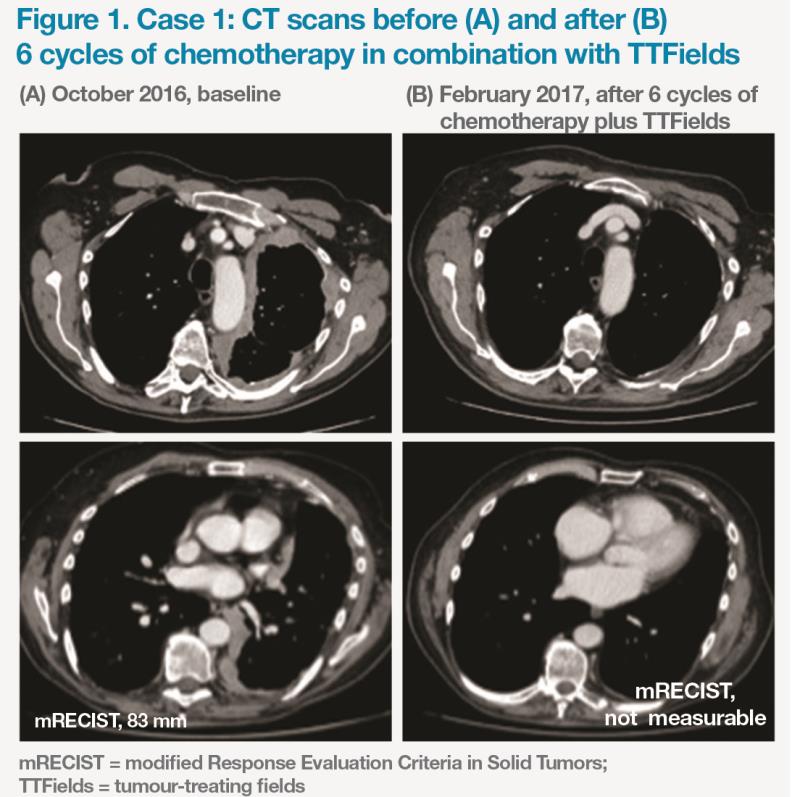

A 70-year-old male patient with epithelioid MPM was commenced on TTFields plus carboplatin/pemetrexed in October 2016. After six cycles of combination therapy, the tumour was non-measurable. (Figure 1) Treatment was well tolerated, with chemotherapy-related grade 3 anaemia as the only reported AE. The patient continued TTFields as maintenance treatment for four more cycles until developing grade 2 skin toxicity.

The patient’s outcome has been favourable, with a PR (near-complete response) and no disease progression for 10 months. Currently, the patient is receiving second-line treatment for MPM. His OS is 48 months as of November 2020.